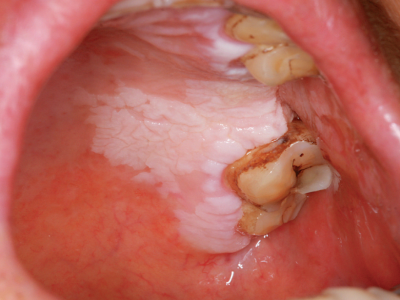

牙龈

白斑

口腔白斑病牙龈有一小块白色斑块图

口腔白斑病症状轻微时,患者的牙龈表面有一小块白色斑块,表现为轻度隆起或高低不平的损害形态,患处有木涩感,对冷热刺激和触觉不太敏感。